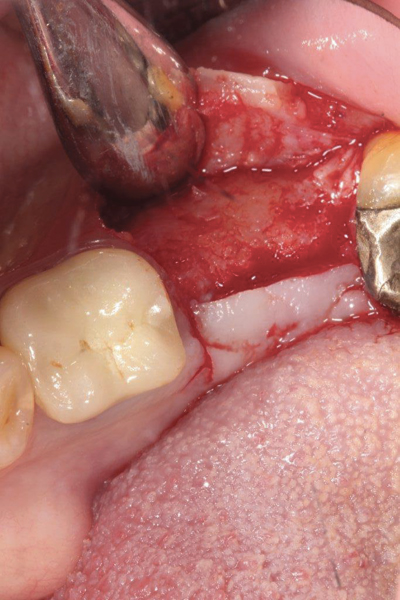

Fig 17. Bone graft was placed in the socket and a d-PTFE barrier was used to cover the graft. The bone graft material was placed beyond the alveolar housing to accommodate shrinkage of graft material and to facilitate attaining a wide alveolar ridge. The barrier was removed after 6 weeks.

Figure 17

The four presented cases shown in Figure 1 through Figure 25 were all treated in a similar manner as outlined in detail in the captions for the first case (Figure 1 through Figure 11). In all four cases, teeth with pathosis were removed, buccal and lingual flaps were elevated, and sites were surgically debrided. A Cytoplast d-PTFE barrier was sized and inserted usually under the buccal flap, the bone graft was added, the barrier was then tucked under the lingual flap, and the flaps were sutured. Bone grafts were used in all of the cases, because buccal bony plates were resorbed and the bone graft helped support the barrier.